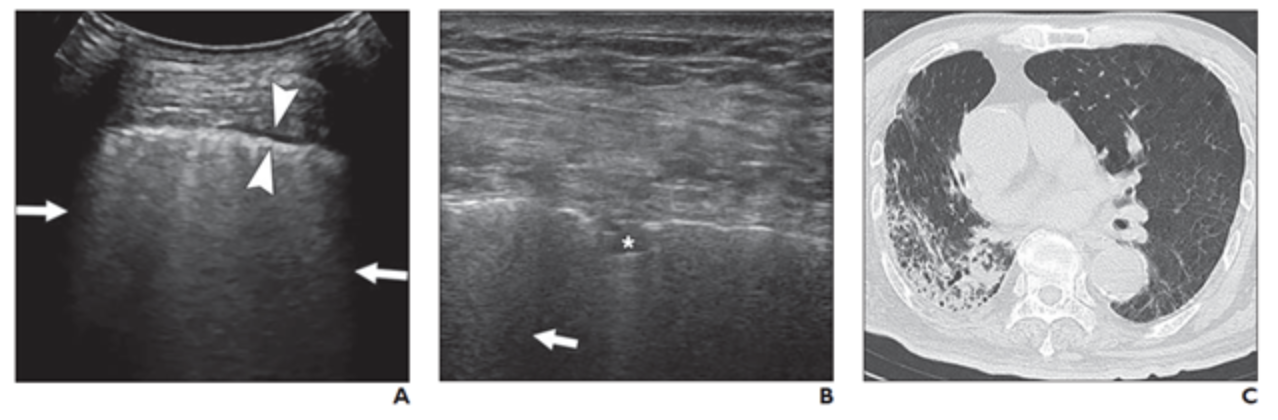

A and B, Lung ultrasound images obtained with convex (A) and linear (B) probes. Multiple confluent B-lines (arrows), patchy pulmonary consolidation (asterisk, B), and thickened pleural line (between arrowheads, A) are visualized. C, Chest CT image shows reticular and interlobular septal thickening and patchy, focal opacities associated with architectural distortion. This patient was classified in critical group and was assigned to severe group for statistical analysis.

July 23, 2020 — According to an open-access article published in ARRS’ American Journal of Roentgenology (AJR), lung ultrasound (US) was highly sensitive for detecting abnormalities in patients with coronavirus disease (COVID-19), with B-lines, a thickened pleural line, and pulmonary consolidation the most commonly observed features.

All 28 patients (14 men and 14 women; age range, 21–92 years) had positive findings on both lung US and chest computed tomography (CT). On US, B-lines were present in 100% of patients, and 19 (67.9%) patients had pulmonary consolidation. Thickened pleural lines were observed in 17 patients (60.7%), and only one patient (3.6%) showed a small amount of pleural effusion.

“A thickened pleural line was more frequently observed on US in patients with longer time intervals after the initial onset of symptoms,” Zhang et al. noted, adding that pulmonary consolidations — visualized as tissuelike hypoechoic regions, reflecting highly reduced air flow and increased quantity of inflammatory cellular exudate—were more common in severe and critical cases.